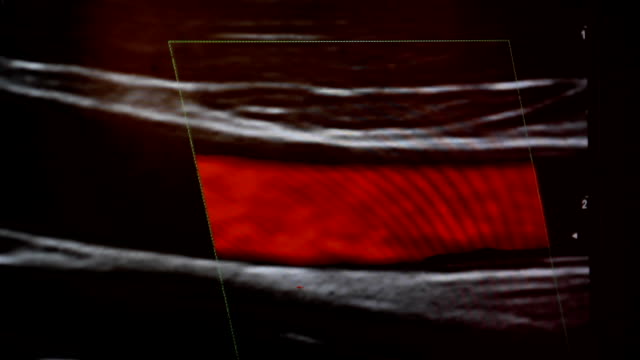

경동맥 초음파 검사의 원리

경동맥 초음파 검사는 초음파 기계를 사용하여 경동맥의 상태를 확인하는 검사입니다. 이 검사는 무해하고 비침습적이며, 빠르게 수행할 수 있어 환자에게 불편함을 주지 않습니다. 검사 과정은 다음과 같습니다.

- 초음파 프로브는 고주파 소리파장을 방출하여 경동맥의 이미지를 생성합니다.

- 이미지를 컴퓨터 모니터에 표시하여 의사가 경동맥의 상태를 시각적으로 확인할 수 있습니다.

- 혈류 속도: 혈액이 경동맥을 흐르는 속도를 측정하여 혈액순환에 이상이 없는지 확인합니다.